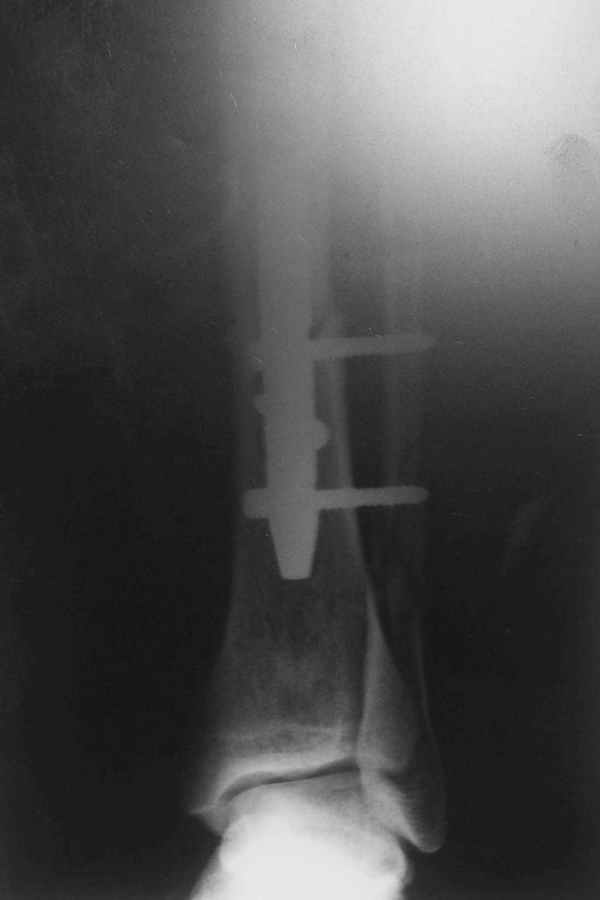

Не удается отправить первичные снимки. А что скажите по имеющимся?!

Выполненный остосинтез нестабилен. Штифт надо заменить по "размеру" на солидный, дистльно три запирающих винта. Успехов!

Перелом спиральный, то есть низкоэнергетический, так что со сращением дело обстоит уже неплохо, лишь бы "костоеда" не развилась. Отломки выглядят уже стабилизированными костной мозолью, так что довводить винты, наверно, уже незачем. Разве что при клинической оценке подвижность еще есть - тогда можно для стабилизации наложить простейший аппарат, не опасаясь контакта его элементов с гвоздем, поскольку места в дистальном метафизе оставлено более чем достаточно.

С Александром согласен, нет необходимости делать дополнительные усилия для сращения, не большая компрессия аппаратом из двух колец и полная нагрузка доделает работу.

Уже имеется какое-то сращение. А в этих условиях выполнить реостеосинтез гвоздём не дольше, чем "накинуть" аппарат из двух колец. Ходить можно сразу с полной нагрузкой, да и качество жизни пациента без аппарата лучше.